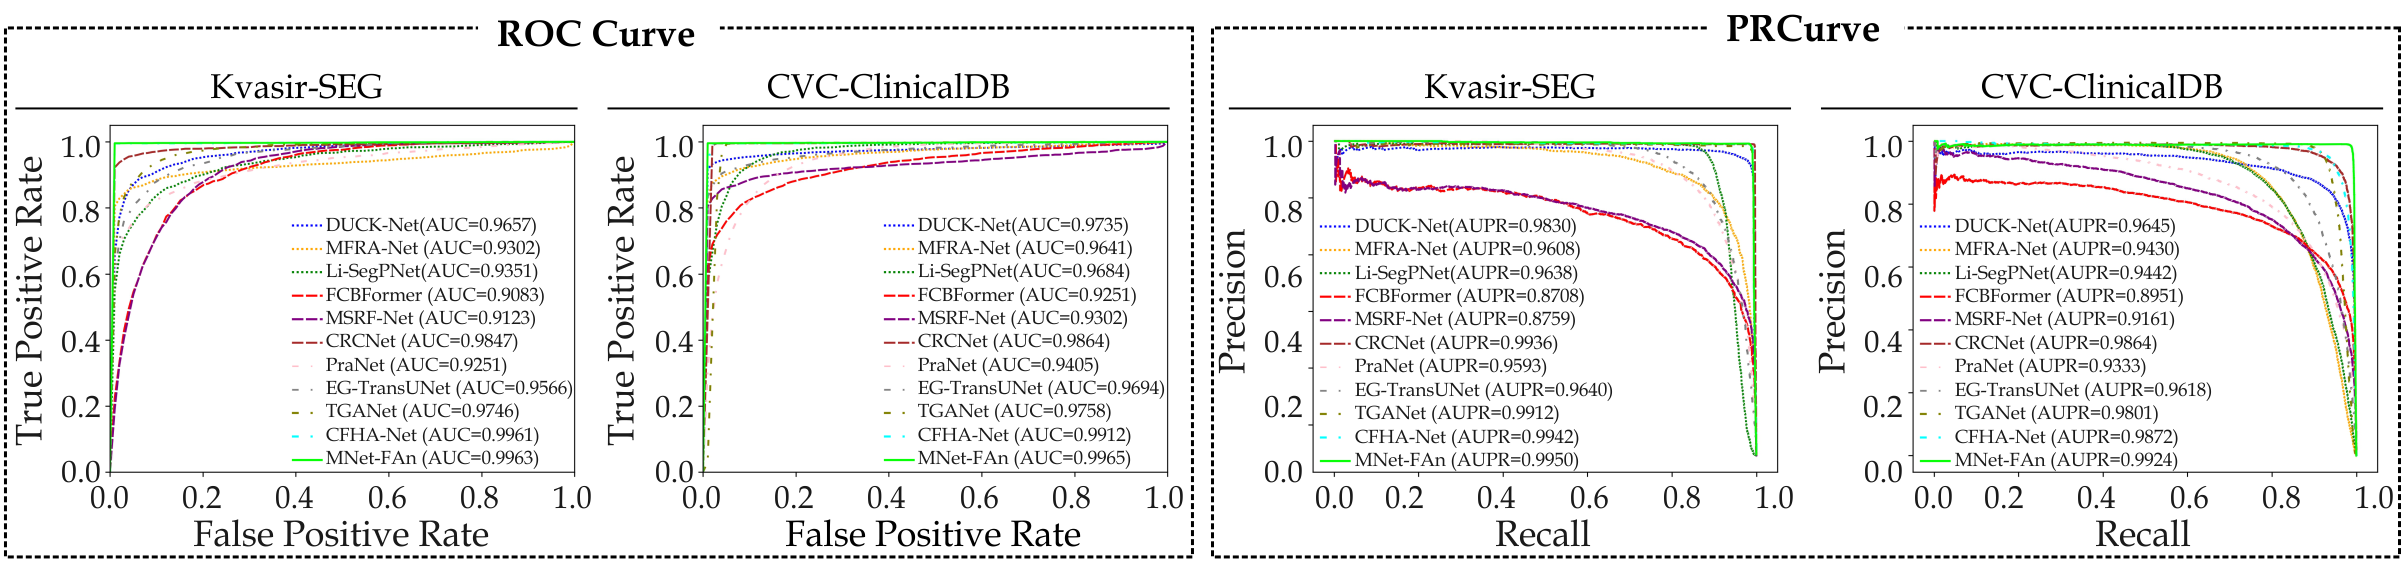

Quantitative Evaluation

Table 2 summarizes the quantitative results from a comprehensive evaluation of the Kvasir-SEG and CVC-ClinicalDB datasets. Fig. 6 presents the corresponding Receiver Operating Characteristic (ROC) curves and Precision-Recall (PR) curves. Our proposed framework demonstrates superior performance, consistently achieving the highest DSC and IoU scores across both datasets. While Li-SegPNet [10] and EGTransUNet [15] exhibit slightly higher Pre and Rec on CVC-ClinicalDB, these models lack the capability to capture multi-scale features as effectively as our framework. Moreover, the PR curves in Fig. 6 further confirm that our framework demonstrates the best overall balance between Pre and Rec across both datasets. Compared to DUCK-Net [8], our proposed framework demonstrates a 1.05% and 1.45% improvement in DSC on the Kvasir-SEG and CVC-ClinicDB datasets, respectively. Additionally, MNet-SAt exhibits comparable performance to MSRF-Net [12] and MFRA-Net [9] in terms of Pre and Rec on the Kvasir-SEG dataset. On CVC-ClinicDB, our framework achieves DSC and IoU scores of 98.60% and 95.89%, respectively, outperforming DUCK-Net [8] by 1.45% and CFHA-Net [17] by 0.35%. This quantitative analysis underscores the superior performance of MNet-SAt in polyp segmentation tasks.